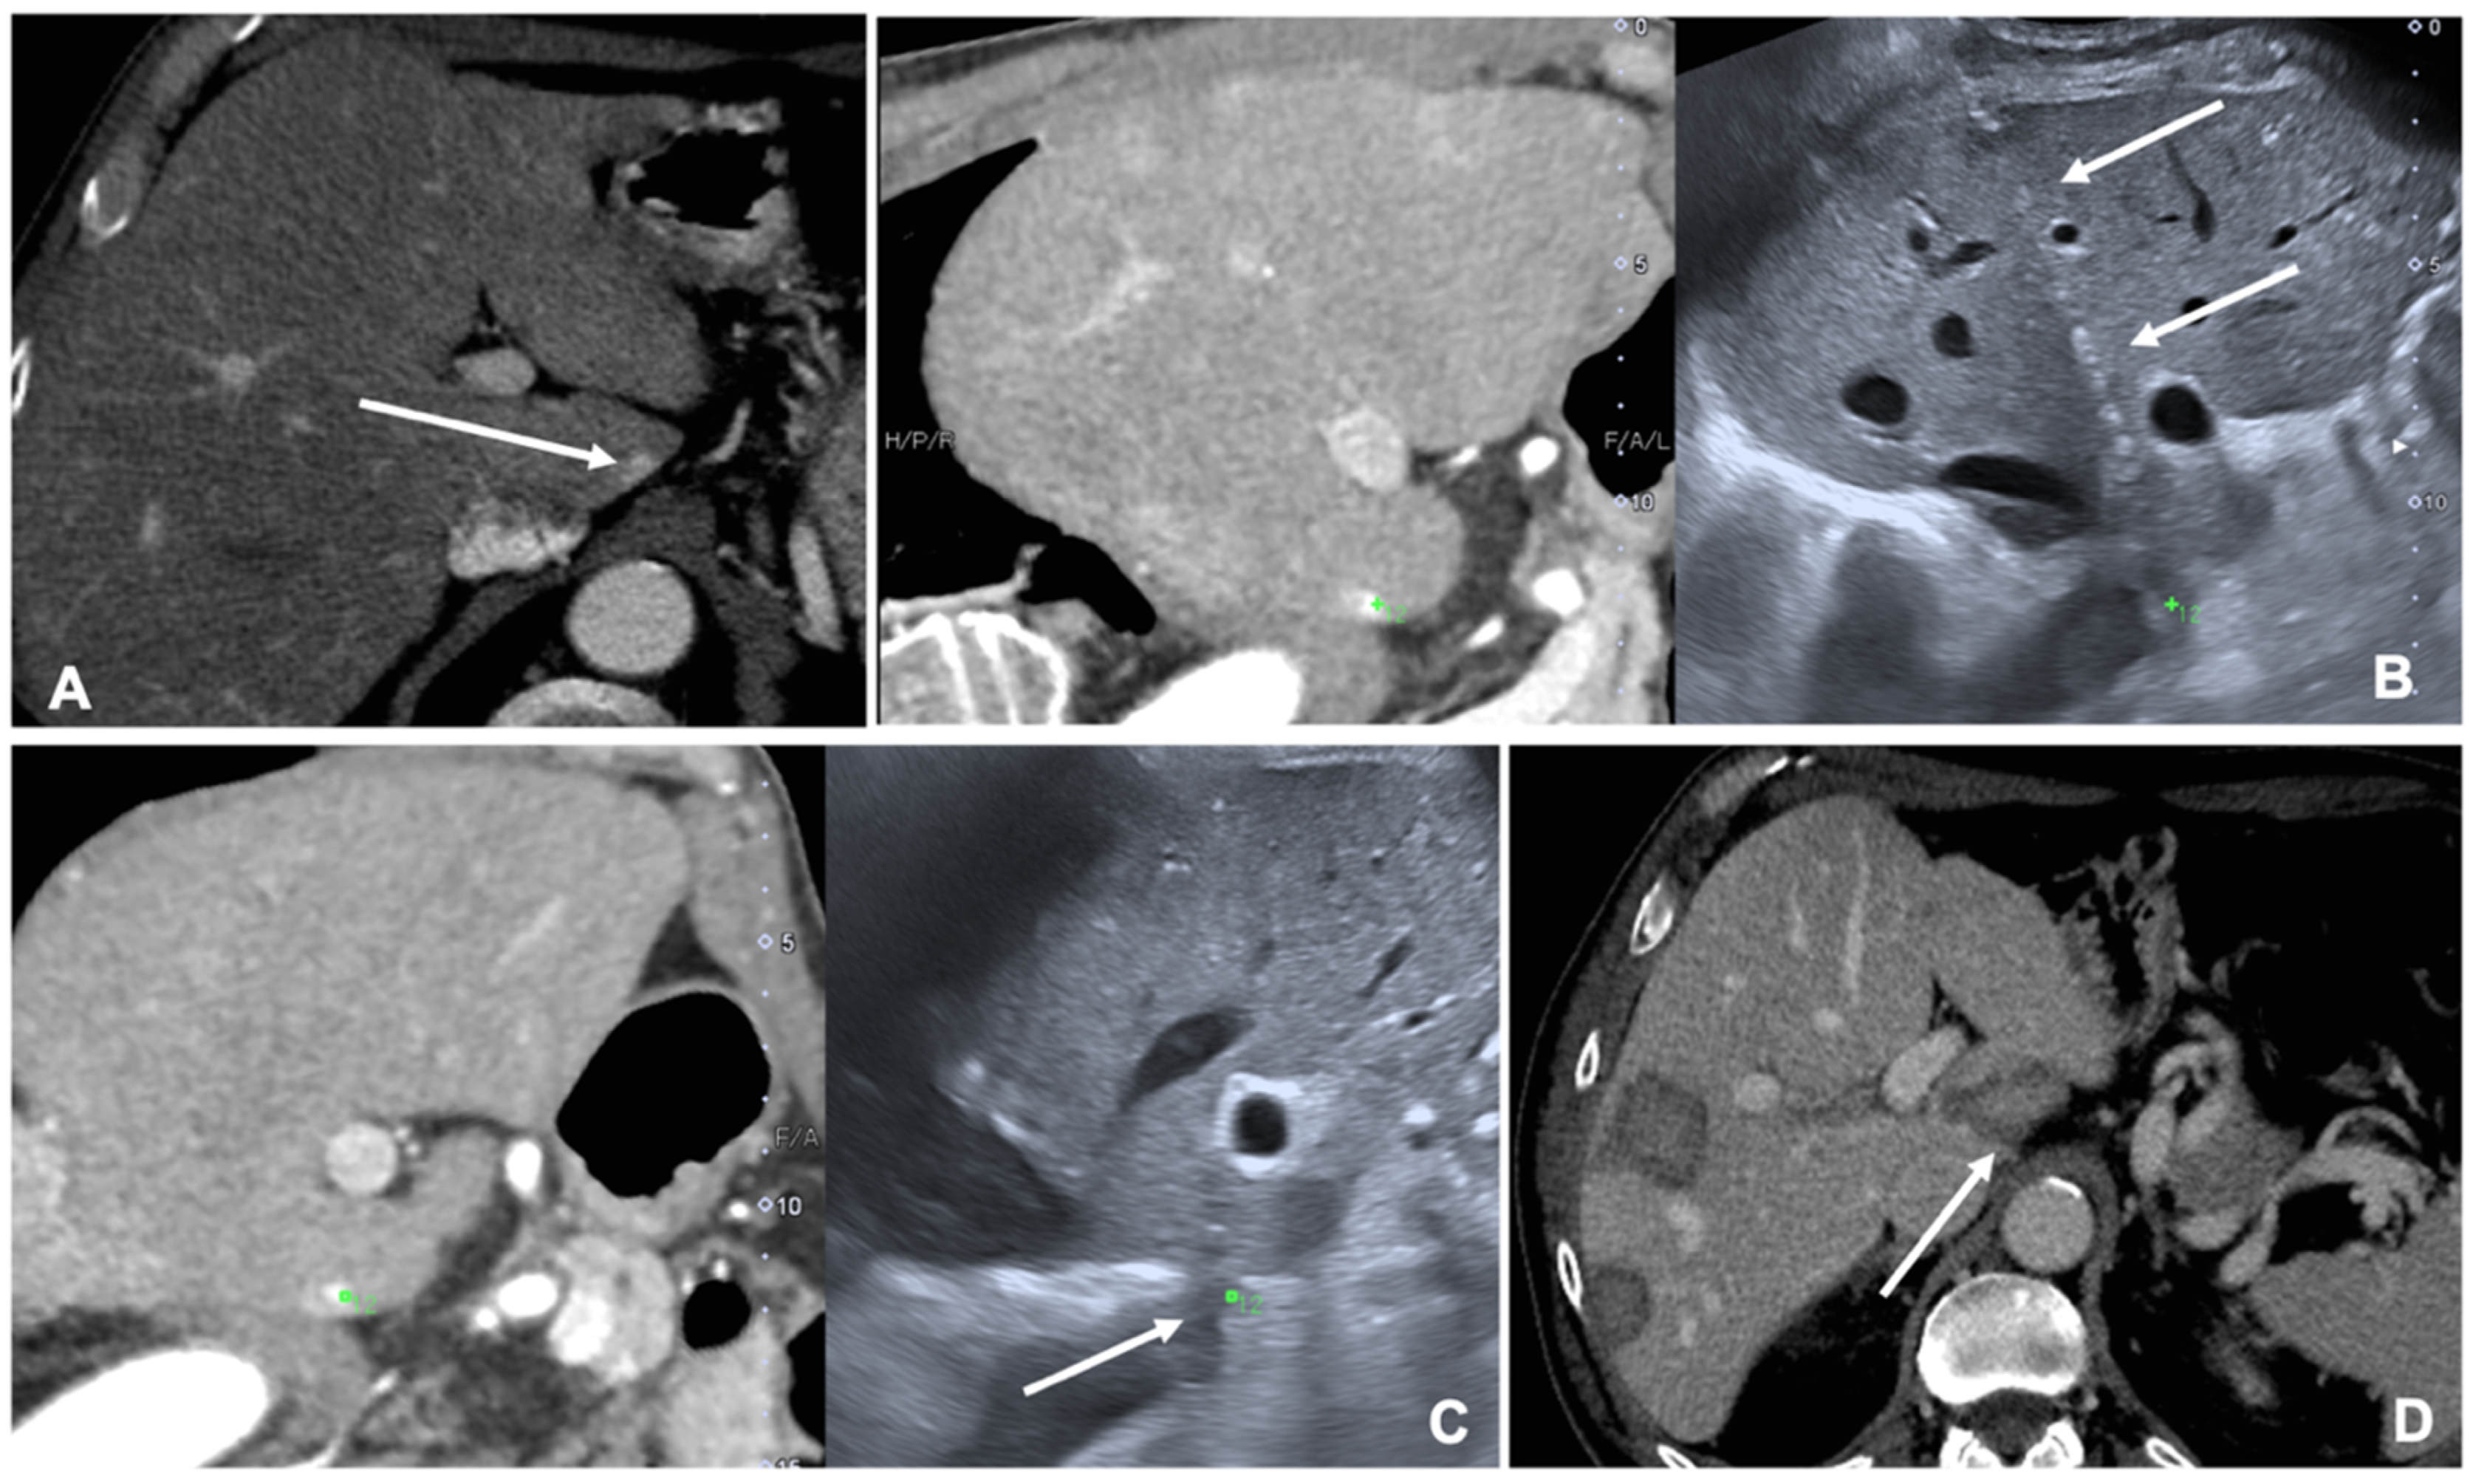

Figure 2. Case of a patient with liver metastases from renal cancer treated with microwave ablation (MWA). (A) Axial view during portal phase of the preoperative contrast enhanced Computed Tomography (CECT) showing a 6 mm enhancing lesion of segment I (white arrow); (B) Live multiplanar reconstruction of the same source CT (left side) using fusion imaging (FI) with intraoperative ultrasound (right side). In both views target lesion is marked by a green spot while the MWA needle is marked by two solid arrows in the ultrasound image (right). (C) FI during MWA of the lesion in the liver segment I. Arrow points out the area of gas formation at the tip of the ablation needle. (D) An axial view of the CECT control the day after the procedure. Arrow points out the area of ablation of the liver segment I.

MRI and CT are both used as reference data set for FI; FI imaging with conventional US and liver CT/MR images improves the detection rate of HCC of 45% and, therefore, the procedure’s feasibility after FI [14,20]. However, some studies have shown the superiority of MRI with hepatobiliary phase to CT images for the identifications and definitions of hepatic lesions, especially in small lesions less than 1 cm [21]. Nevertheless, very promising preliminary data are available regarding US/Cone beam CT (CBCT) FI [22]. It is technically feasible and appears to be an effective image guidance modality for achieving correct targeting and ablation of small lesions not clearly visible at US (Figure 2).